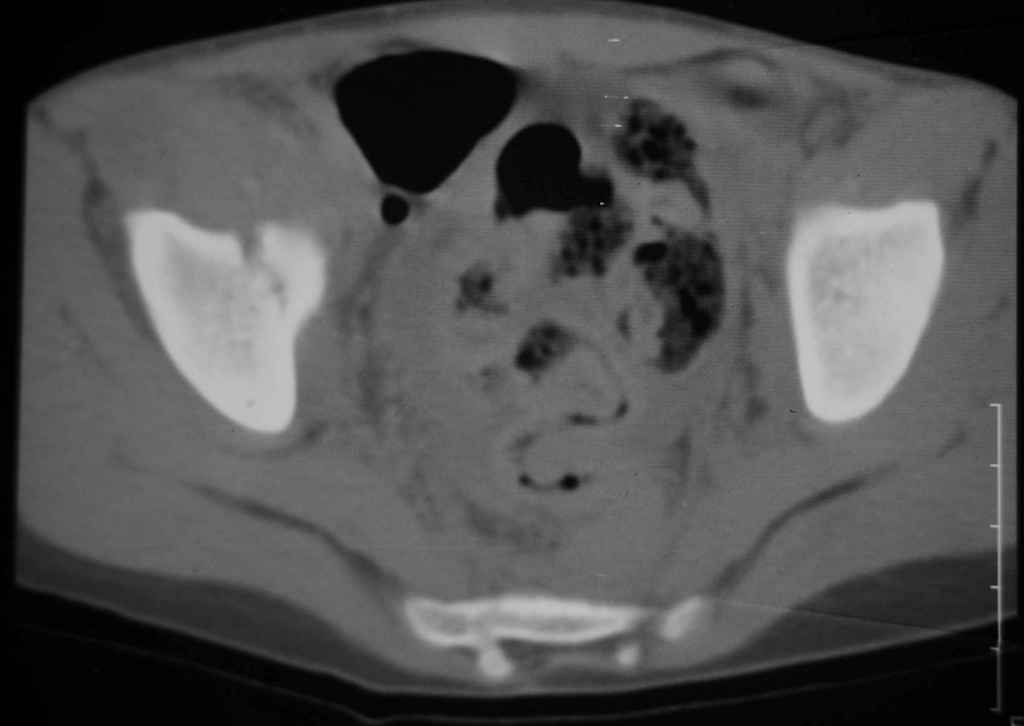

Уважаемые коллеги, помогите определиться с тактикой лечения. Ребёнок 7 лет, травма 11.09.08, поступил с травматическим вывихом бедренной кости.

Вывих вправлен, конечность фиксирована на скелетном вытяжении. Что делать с переломом подвздошной кости? Лечить консерватино или оперировать?